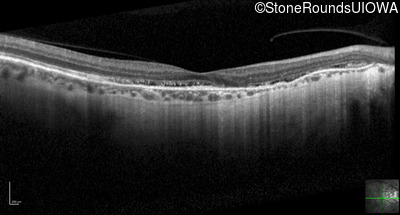

Optical Coherence Tomography - Right - 20/20 -3 sc

Exemplar / OCT Stack

OCT Stack